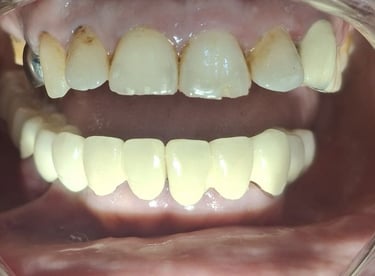

Before

After

All images shown here are real teeth cleaning cases treated at our clinic with patient consent.

Professional teeth cleaning helps remove plaque, tarter, and surface stains that regular at home brushing can not.

At Shree Dental Care, teeth cleaning is performed gently with focus on patient experience, comfort and long term oral health.